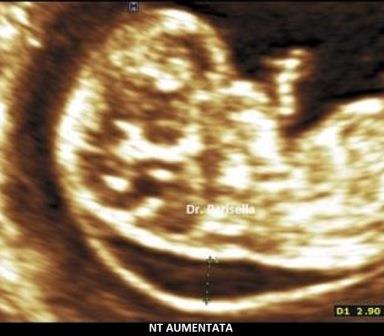

La translucenza nucale è un marker rilevabile tra le 11 settimane + 0 gg. e 13 settimane + 6 gg. di gestazione, più precisamente in un range del CRL compreso tra 45 mm. e 84 mm. Essa appare caratterizzata ecograficamente dall'accumulo sottocutaneo di fluido dietro il collo fetale nel primo trimestre di gravidanza. La Fetal Medicine Foundation (FMF) di Londra ha dettato i criteri da adottare per una corretta misurazione della NT:

- posizionamento dei calipers "on to on": i cursori devono essere posizionati sui bordi interni delle linee che delimitano lo spazio della translucenza nucale senza che le linee orizzontali dei cursori protudano in questo spazio (vedasi immagine)

- la misurazione deve essere eseguita in corrispondenza della parte più ampia della Translucenza

Si è osservato che nei feti sani lo spessore della NT tende ad aumentare con l'incremento del CRL; di conseguenza anche i valori soglia della NT cambiano col variare dei valori del CRL: a 11 settimane con un CRL di 45 mm. i valori possono variare da 1,2 mm. (50° percentile) a 2,1 mm. (95° percentile), mentre a 13 sett. + 6 gg. con un CRL di 84 mm., i valori possono variare da 1,9 mm. (50° percentile) a 2,7 mm. (95° percentile); il 99° percentile non varia col CRL ed è circa 3,5 mm. Si intende per translucenza nucale aumentata uno spessore di NT al disopra del 95° percentile. Con un software dedicato che prende in considerazione NT, CRL, età materna e Frequenza Cardiaca Fetale (FHR), con un cut-off attualmente di 1/100 (Fetal Medicine Foundation) è possibile calcolare il rischio di anomalie cromosomiche con una sensibilità di circa il 90% ed una percentuale di falsi positivi di circa il 5%. La FHR assume notevole importanza nello screening della Trisomia 13: infatti circa l'85% dei feti con Trisomia 13 hanno una frequenza cardiaca al disopra del 95° percentile; nella Trisomia 21 solo il 15% dei feti ha un lieve aumento della FHR oltre il 95° percentile, mentre nella Trisomia 18 solo il 15% dei feti ha una lieve diminuzione della FHR al disotto del 5° percentile.

Nei feti in cui vi è una NT aumentata e cariotipo normale viene riportata una maggiore frequenza di cardiopatie congenite, displasie scheletriche, sindromi genetiche, anomalie strutturali.

Le principali anomalie congenite associate alla NT aumentata e cariotipo normale sono le cardiopatie congenite.